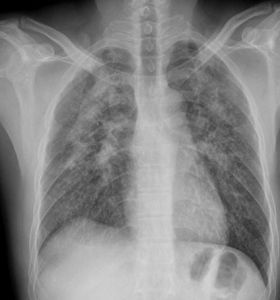

2.X線表現

X線胸片是診斷矽肺的主要方法。主要表現為結節陰影(直徑一般在1~3mm)、網狀陰影或(和)大片融合病灶。其次為肺門改變、肺紋理改變和胸膜改變。接觸矽塵含量高和濃度大的矽肺患者,常以圓形或類圓形陰影為主,早期出現於兩中下肺的內中帶,以右側為多,隨後逐漸向上擴展,亦可先出現在兩上肺葉。含矽塵量低或為混合性粉塵,多以類圓形或不規則陰影為主。大陰影一般多見於兩肺上葉中外帶,常呈對稱性具跨葉的八字形,其外緣肺野透亮度增高。因大塊肺纖維化收縮使肺門上移,使增粗的肺紋呈垂柳狀,並出現氣管縱隔移位。肺門陰影密度增加,有時可見“蛋殼樣鈣化”的淋巴結。胸膜可有增厚、粘連或鈣化的改變。